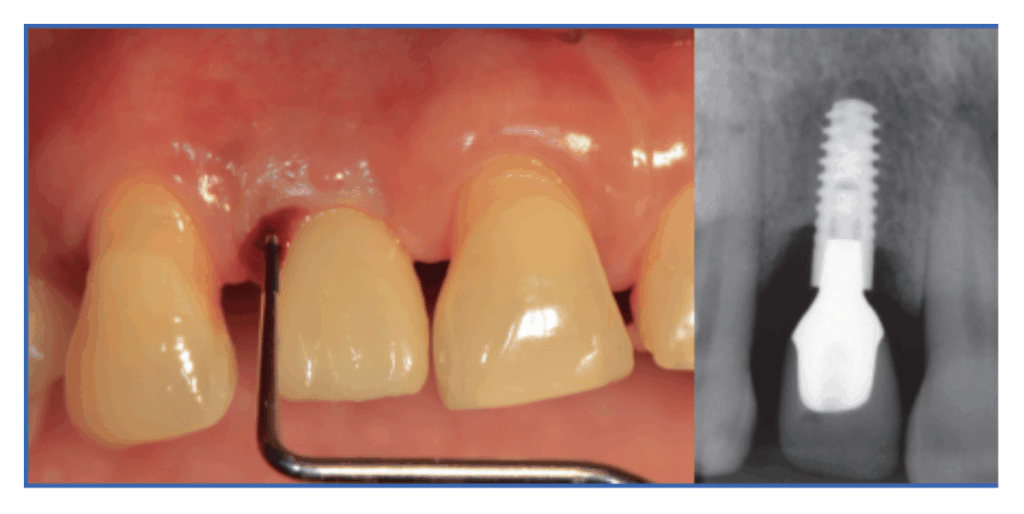

- Sondaje suave para valorar sangrado, supuración y profundidad de bolsa periimplantaria (periimplantitis).

- Radiografías periapicales y, si se necesita, CBCT para medir la pérdida ósea de periimplantitis.